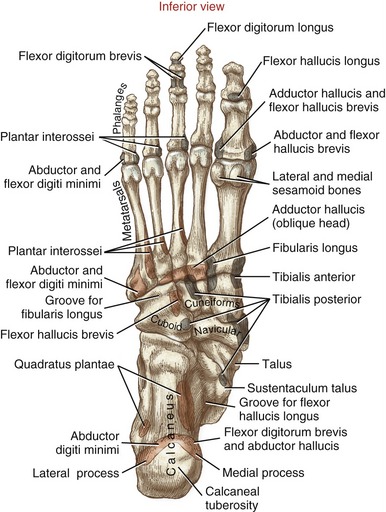

Osteology & Attachments

• Superior view

• Inferior view

• Medial view

• Lateral view

Columns

• Medial

• 1st metatarsal

• medial cuneiform

• navicular

• talus

• Middle

• 2nd + 3rd metatarsals

• middle + lateral cuneiforms

• Lateral

• 4th + 5th metatarsals

• cuboid

• calcaneus